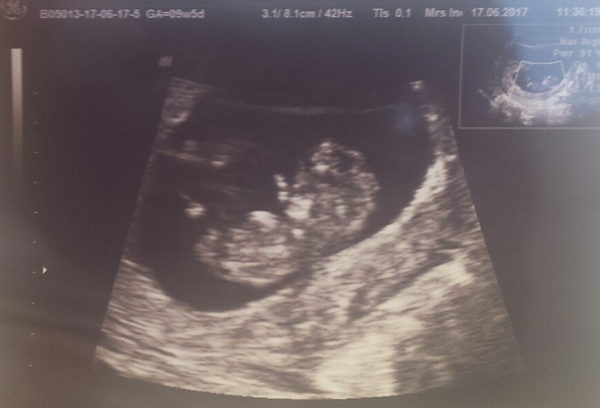

alins · 17/06/2017 15:30

Happy to say baby is doing great!

Just being very lazy as didn't want to move much!

By the measurements I am 10 weeks and 2 days so 4 days ahead and everything is looking great!

Now I can relax for a few days!

Brilliant alins! So happy for you! What a lovely pic!

Aw congratulations! What a lovely pic - it actually looks like a baby if that makes sense. My DH surprised me today with a package of 5 scans throughout pregnancy which I'm thrilled with given how impatient (and worried!) I get about this!

alins lovely scan picture. So glad everything is looking good with baby.